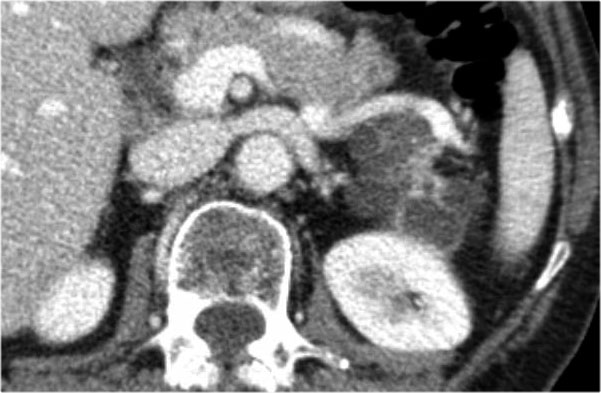

Một ví dụ khác về u nang tuyến thanh dịch (Hình).

Hình ảnh sau tiêm thuốc cản quang bên phải cho thấy tổn thương giảm tỷ trọng với vôi hóa trung tâm ở thân tụy và ngấm thuốc nhẹ của các vách ngăn.

Lưu ý rằng trên CT rất khó nhận ra bản chất dạng nang của các tổn thương này và có thể nhầm lẫn với ung thư biểu mô tuyến tụy.

MRI sẽ dễ dàng thể hiện bản chất dạng nang của các tổn thương này (hình).

Chuỗi xung T2W với xóa mỡ (fatsat) thể hiện rõ tổn thương tăng tín hiệu dạng thùy múi với sẹo trung tâm, đây là hình ảnh đặc trưng của SCN.